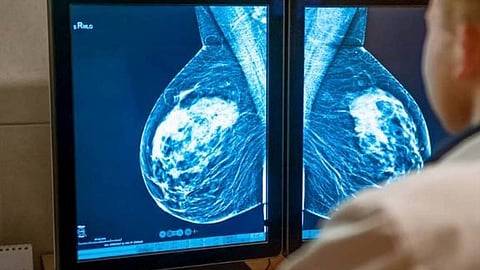

خلصت دراسة قدمت خلال الندوة الـ43 لسرطان الثدي في سان أنطونيو بالولايات المتحدة، إلى إمكانية علاج ما يصل إلى 20% من النساء المصابات بسرطان الثدي، بدون علاج كيميائي.

وقالت الدراسة إن من بين الأنواع الفرعية المختلفة لسرطان الثدي، فإن ما يسمى بـLuminal هو الأكثر شيوعًا، لكن العديد من النساء اللائي يعانين منه سيتمكن من تجنب العلاج الكيميائي المعتاد.